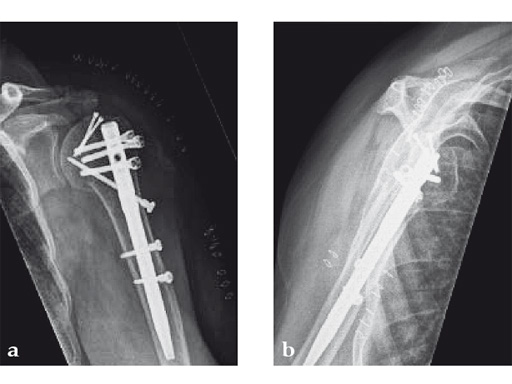

Following a fall downstairs, a 70-year-old woman sustained a head injury with intracerebral and subdural haematoma, as well as a complex fracture of the right humerus, representing a minimal displaced proximal and an oblique fracture in the distal part of the humerus (Fig 11).

After neurosurgical intervention, surgery of the humerus was planned 10 days after the index trauma. The patient was still at the neurological intensive care unit and a preoperative clinical examination of the patient, regarding radial nerve palsy, was not possible. Therefore, a surgical revision with exploration of the radial nerve and an osteosythesis of the humerus using a long MultiLoc Humeral Nail was indicated.

The patient was operated on in beach chair position. For the exploration of the radial nerve, a limited anterolateral approach was used. The nerve was mobilized and retracted laterally. An anterolateral approach to the proximal humerus was performed. The supraspinatus showed a small acute rupture without retraction. The supraspinatus tendon was split to get access to the insertion area on the humeral head. A 270 mm long MultiLoc Humeral Nail of 8.5 mm diameter was inserted under visual and x-ray control to the desired endpoint. Reduction of both the proximal and the distal humerus fracture was anatomical. In the lateral view there was a small gap, and it was decided to apply compression after distal locking (Fig 12). Proximally, three MultiLoc screws were inserted and a 2 mm end cap was placed. Finally, the supraspinatus rupture was reconstructed with transosseous sutures and secured with an augmentation plate. The posterior greater tuberosity fracture was secured with Fiber Wire to the MultiLoc screws. Fig 13 illustrates the definitive fixation.

Postoperatively, no sling was used because the patient stayed in medically induced coma.